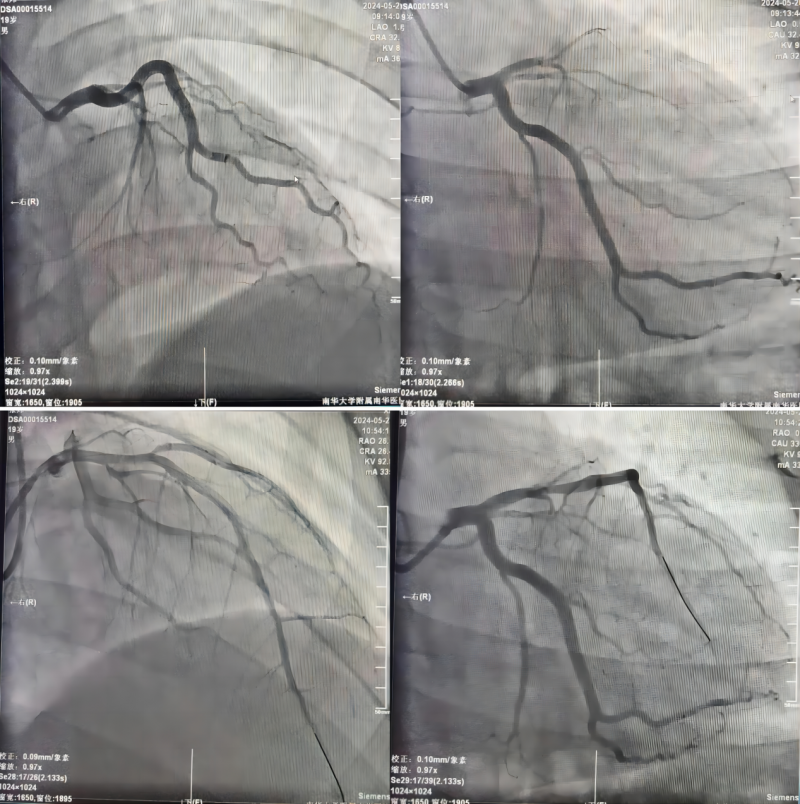

经过周密的检查和评估,胸痛中心团队发现小张的冠状动脉前降支近段存在严重闭塞。面对小张对支架植入的强烈抵触情绪,李招兵主任医师、江振涛副主任医师等组成的介入团队进行了深入的讨论和沟通。他们充分尊重患者的意愿,最终决定采用一种更为温和、侵入性更小的治疗方法——通过反复抽吸病变处的血栓,并使用球囊扩张血管,以恢复血流,保障心脏的正常血液供应。

△手术前(上)、后(下)对比

手术取得了圆满成功,小张的心脏功能得到了迅速恢复。在术后康复期间,医疗团队不仅关注小张的身体健康状况,还积极关注他的心理状态和学习进度。他们为小张制定了个性化的康复计划,并提供心理支持,确保他在身心两方面都能得到良好的恢复。在他们的精心照料下,小张逐渐康复,重新找回了对生活的热爱和对未来的憧憬。